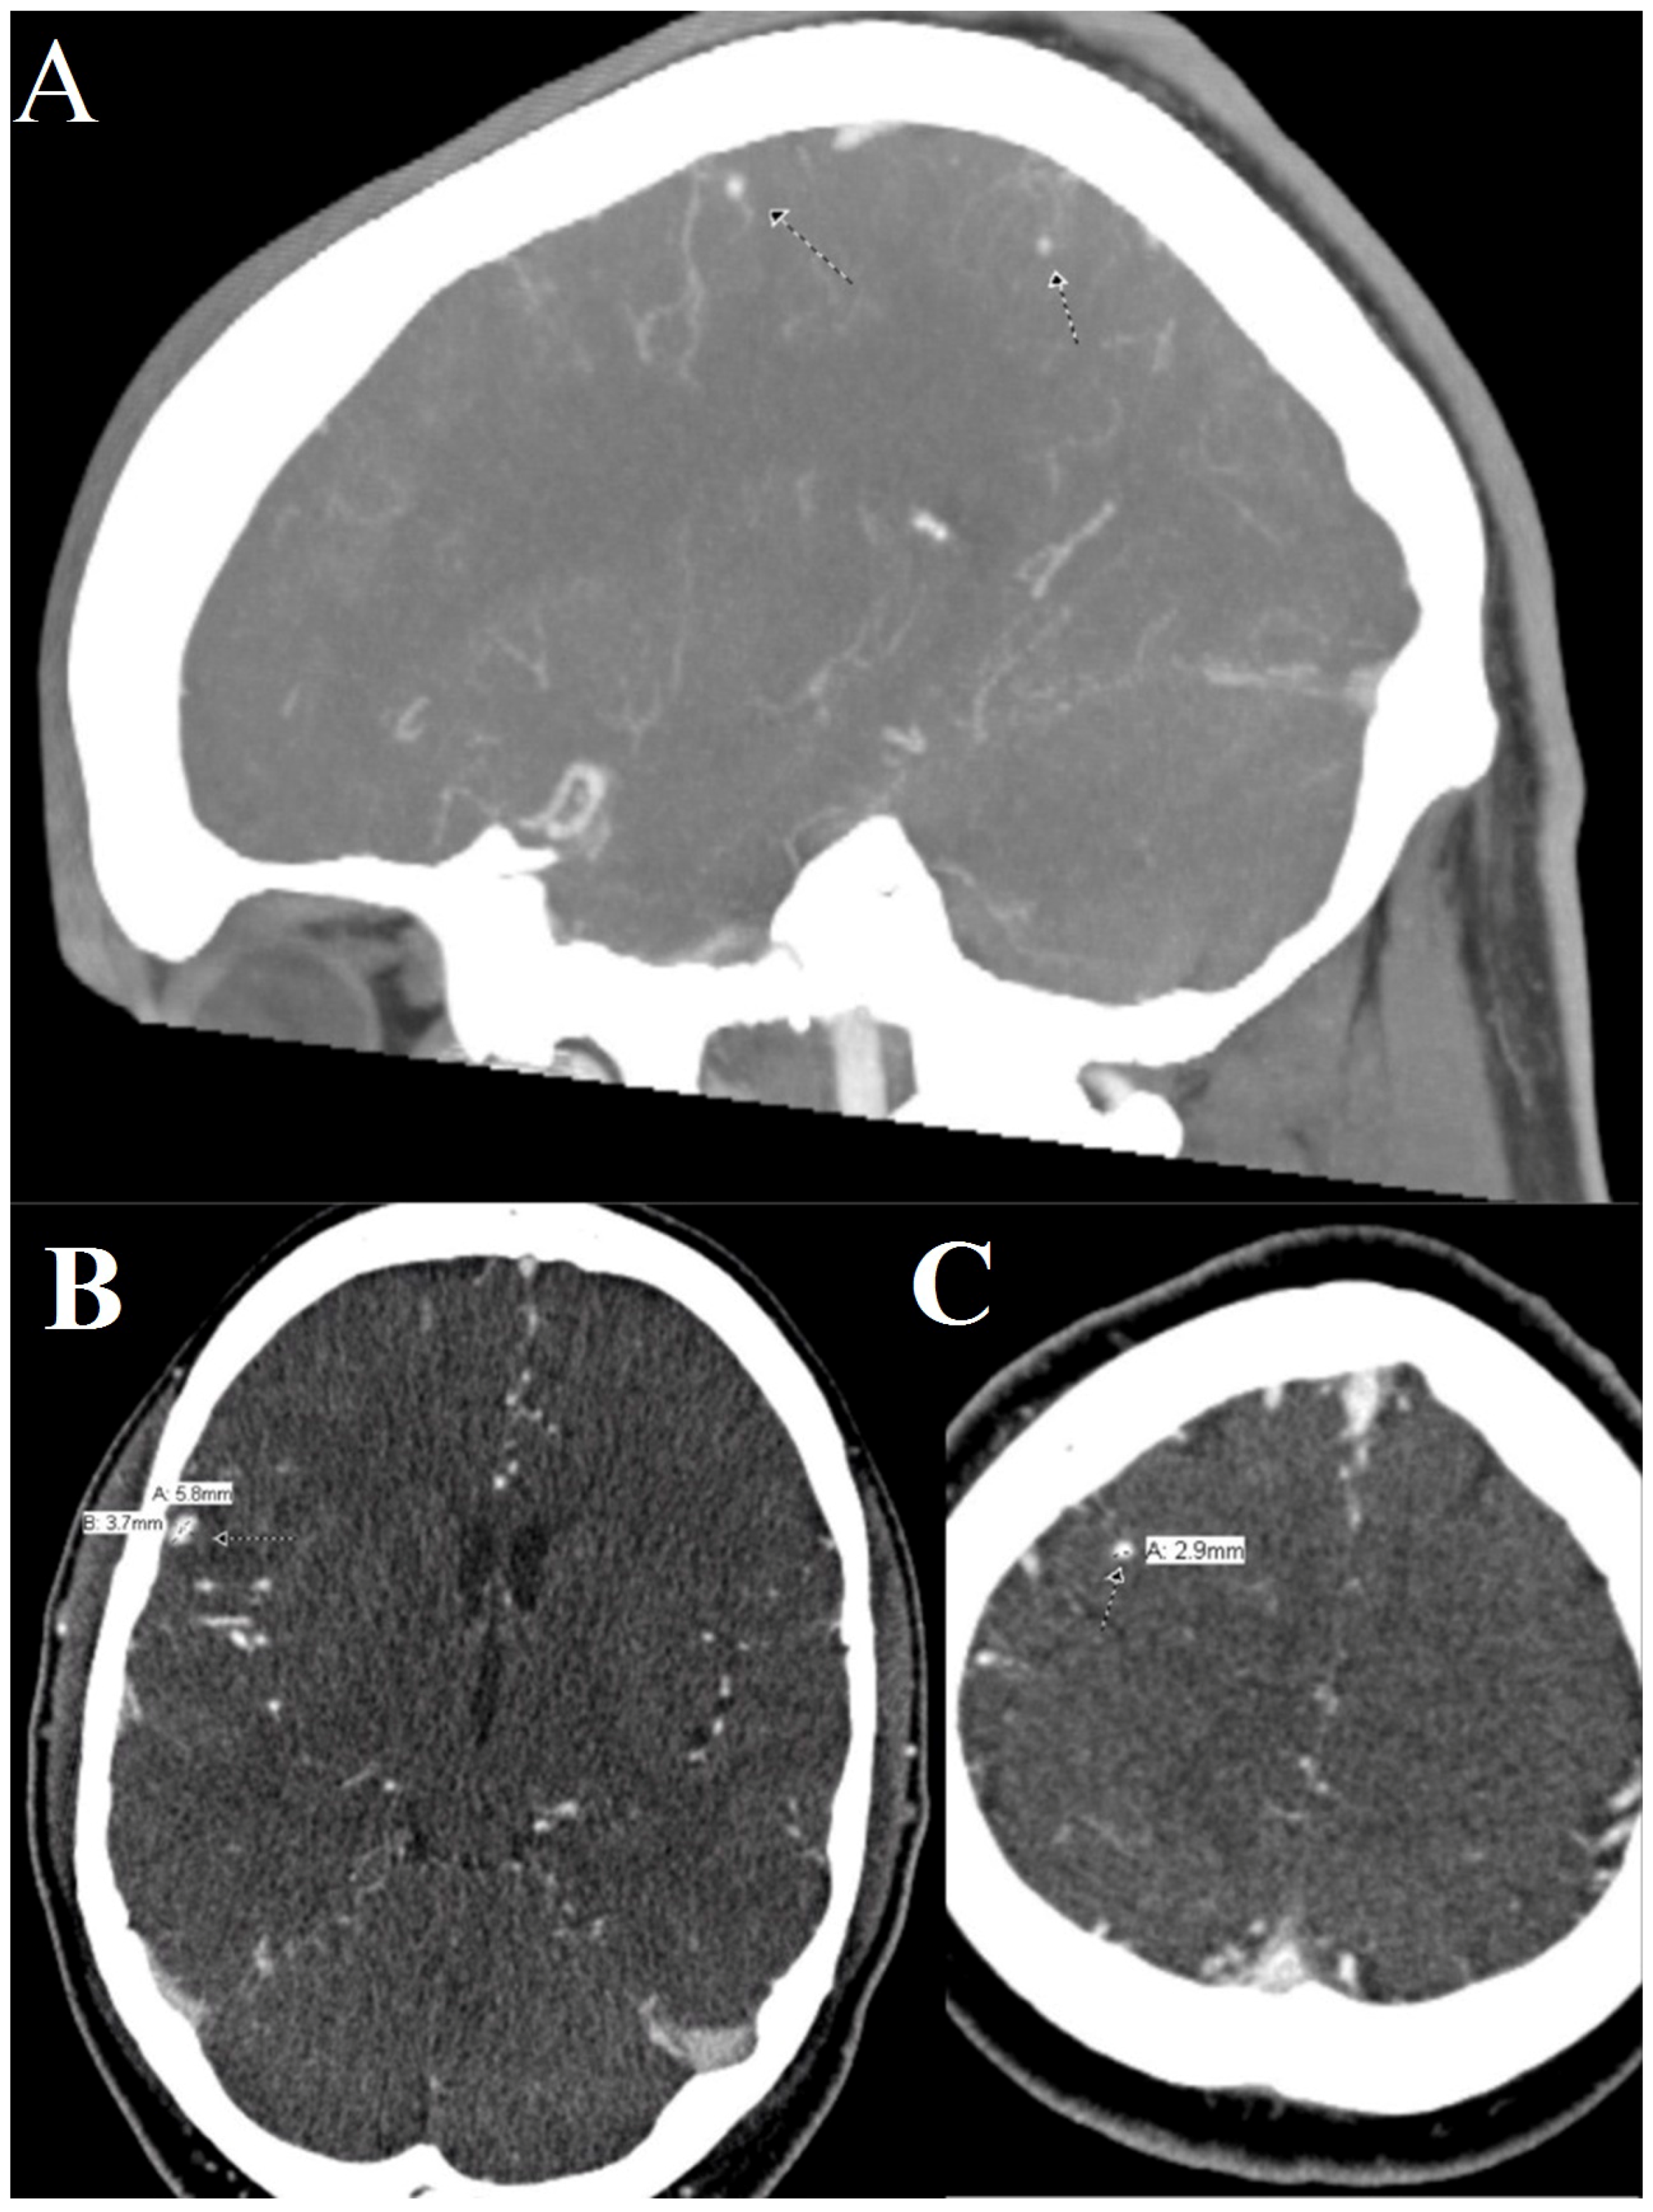

First Time Seizure in the Setting of a Congenital Heart Abnormality and MCA Mycotic Aneurysms

1. Clinical Presentation